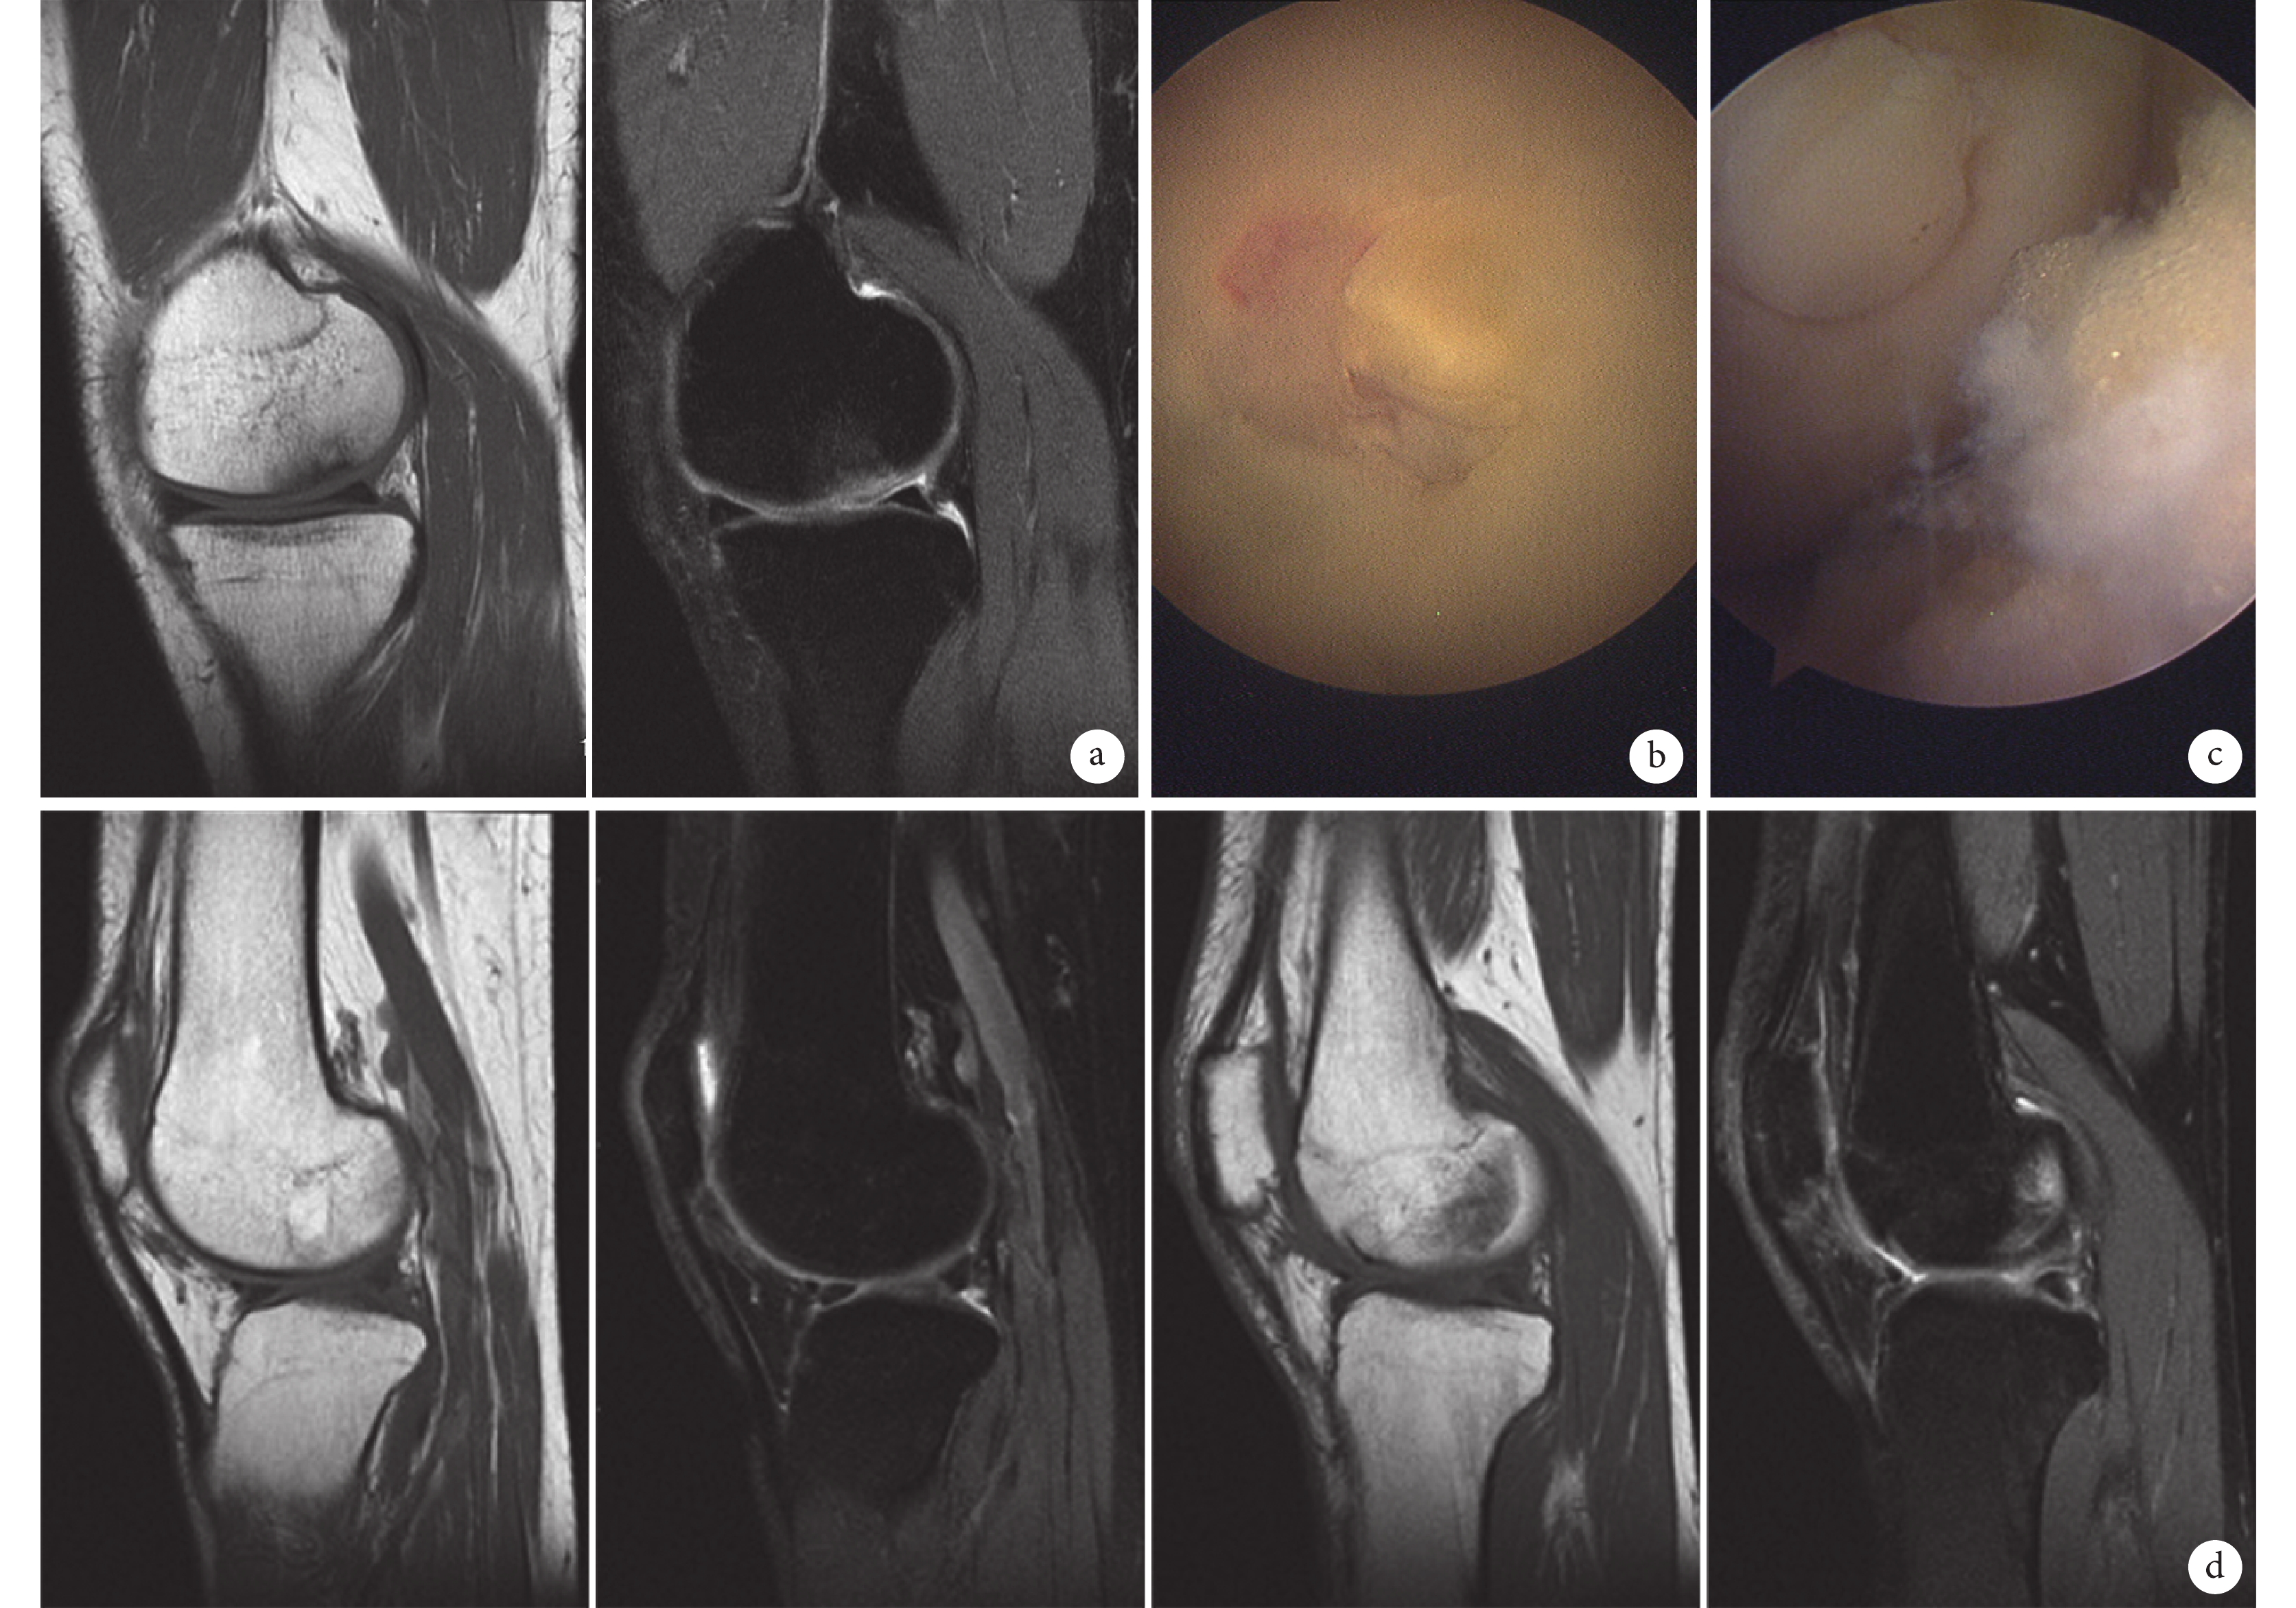

兩組術后切口均Ⅰ期愈合,無感染等手術早期并發癥發生。兩組患者均獲隨訪,隨訪時間 2~8 年,平均 3.6 年。 兩組術后 2 年膝關節 Lysholm 評分、IKDC 評分均較術前顯著提高,差異有統計學意義(P<0.05);術前及術后 2 年時,青年組 Lysholm 評分及 IKDC 評分均明顯優于中年組(P<0.05);但兩組手術前后評分差值比較,差異均無統計學意義(P>0.05)。見表 1。術后 2 年,MRI 復查示兩組供區中央區有正常軟骨生成,供區骨洞完全被新生骨質填充;受區軟骨厚度及 MRI 信號與周圍軟骨相似,骨質與周邊骨質完全愈合。見圖 1、2。

a. 術前 MRI 示股骨內側髁軟骨損傷;b. 術中關節鏡下見股骨內側髁軟骨損傷;c. 術中關節鏡下見自體骨軟骨移植后;d. 術后 2 年 MRI 示供區、受區修復良好

Figure1. A 36-year-old male patient with right articular cartilage injury (ICRS grade Ⅳ) in young groupa. Preoperative MRI showed the cartilage lesion of medial femoral condyle; b. Intraoperative arthroscopic view of the cartilage lesion of medial femoral condyle; c. Intraoperative arthroscopic view after OAT; d. MRI showed both receiving and the donor sites healed well at 2 years after operation